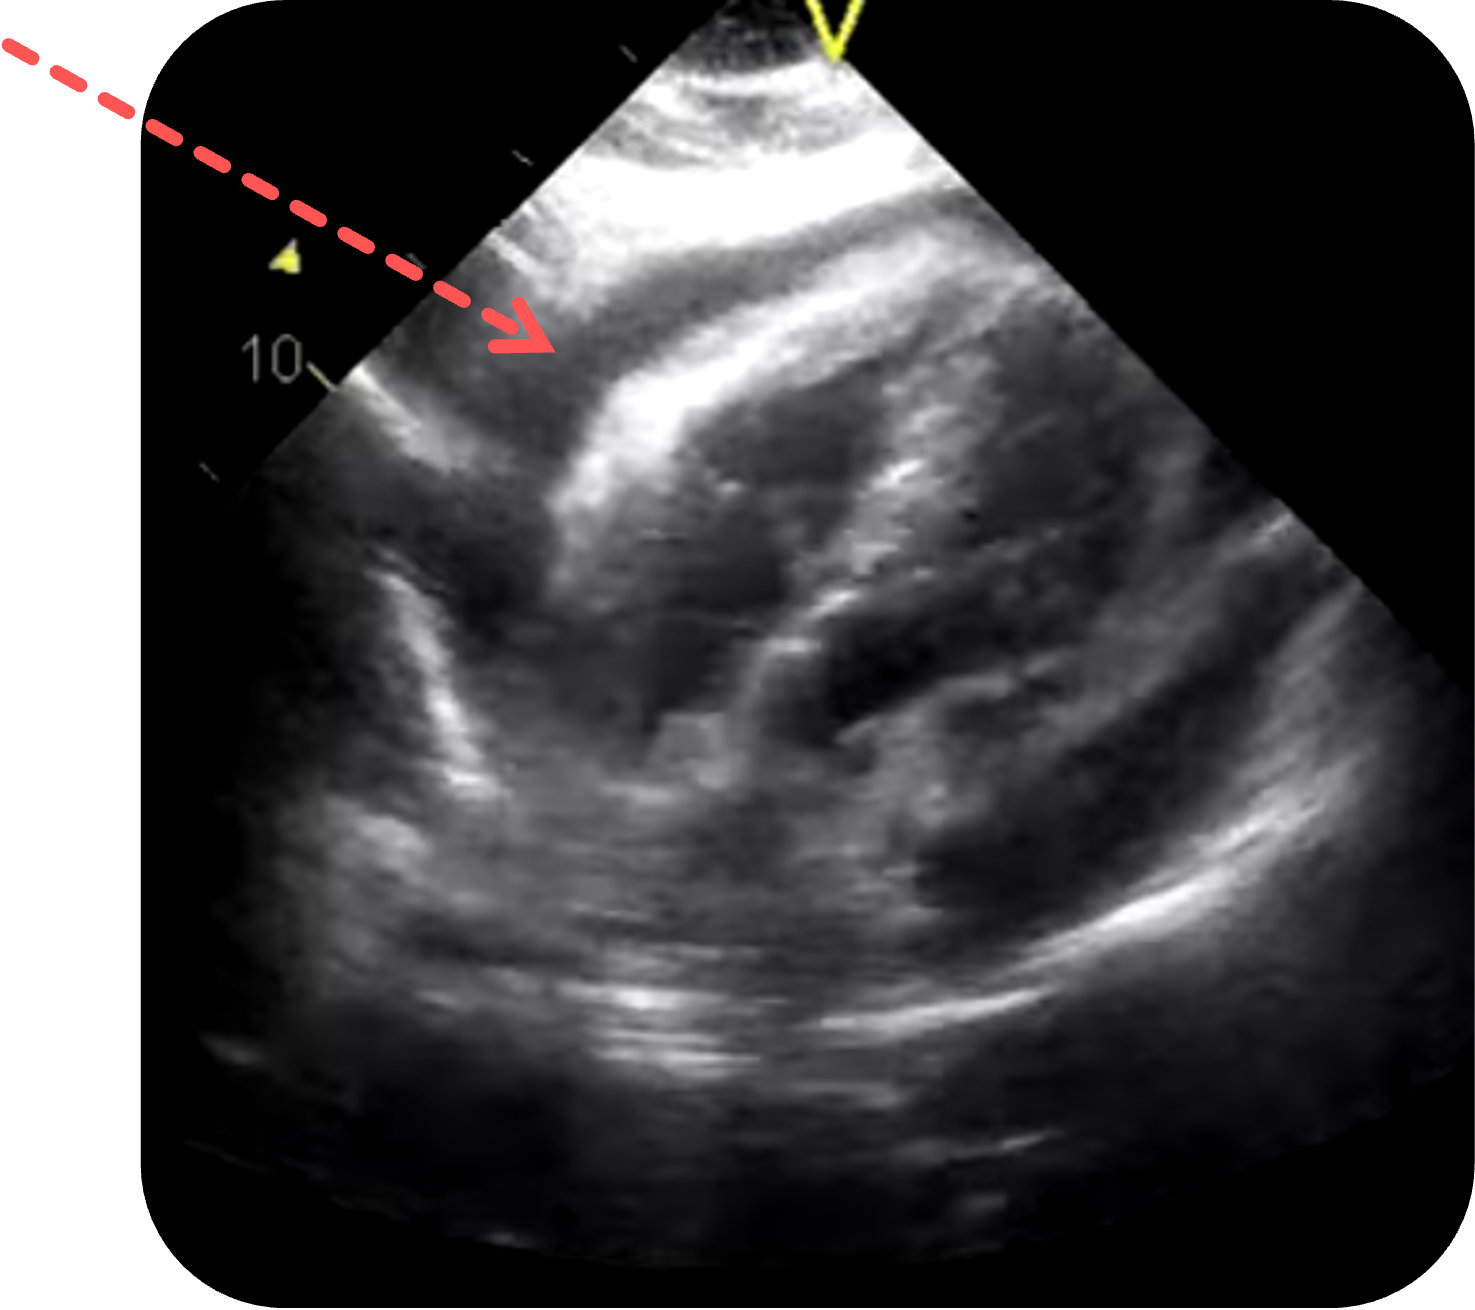

Schritt 1: Sondenposition - Zugangspunkt (Subkostalblick)

- Sonde: Phased-Array

- Ausrichtung: Marker zeigt nach rechts

- Position: Direkt subxiphoidal, flach unter den Rippenbogen geschoben

- Schallwinkel: Möglichst flach zum Thorax

, um Leber als akustisches Fenster zu nutzen - Tipp: Eine tiefe Inspiration

kann für eine bessere Darstellung helfen!

Figure 2 aus Vázquez Martínez, J.L., Quiñones Coneo, K.L., Villegas, T.V. et al. Applicability of a modified EFAST protocol (r-EFAST) to evaluate hemodynamically unstable patients after percutaneous cardiac intervention. Crit Ultrasound J 9, 12 (2017). https://doi.org/10.1186/s13089-017-0070-3. Teilausschnitt des Originalbilds.